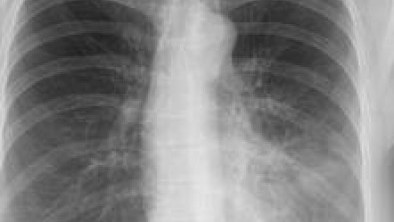

Akciğer zarları arasında hava dolması durumuna akciğer sönmesi denir. Tek başına bir hastalık olmamak ile birlikte birçok sebebe bağlı olarak görülmektedir. Göğüs kafesinin içerisinde üstü hava geçirmeyen ince zarla kaplanmış ve içi hava dolu solunum organlarımızdır.

Çöken akciğerin alanına göre solunum dakika sayısında artma, dudak ve dilde morarma ve taşikardi görülebilmektedir. Kesin tanı akciğer grafisinde akciğerin söndüğü ve o bölgenin şeffaflaştığı görülerek tanı netleşebilmektedir.